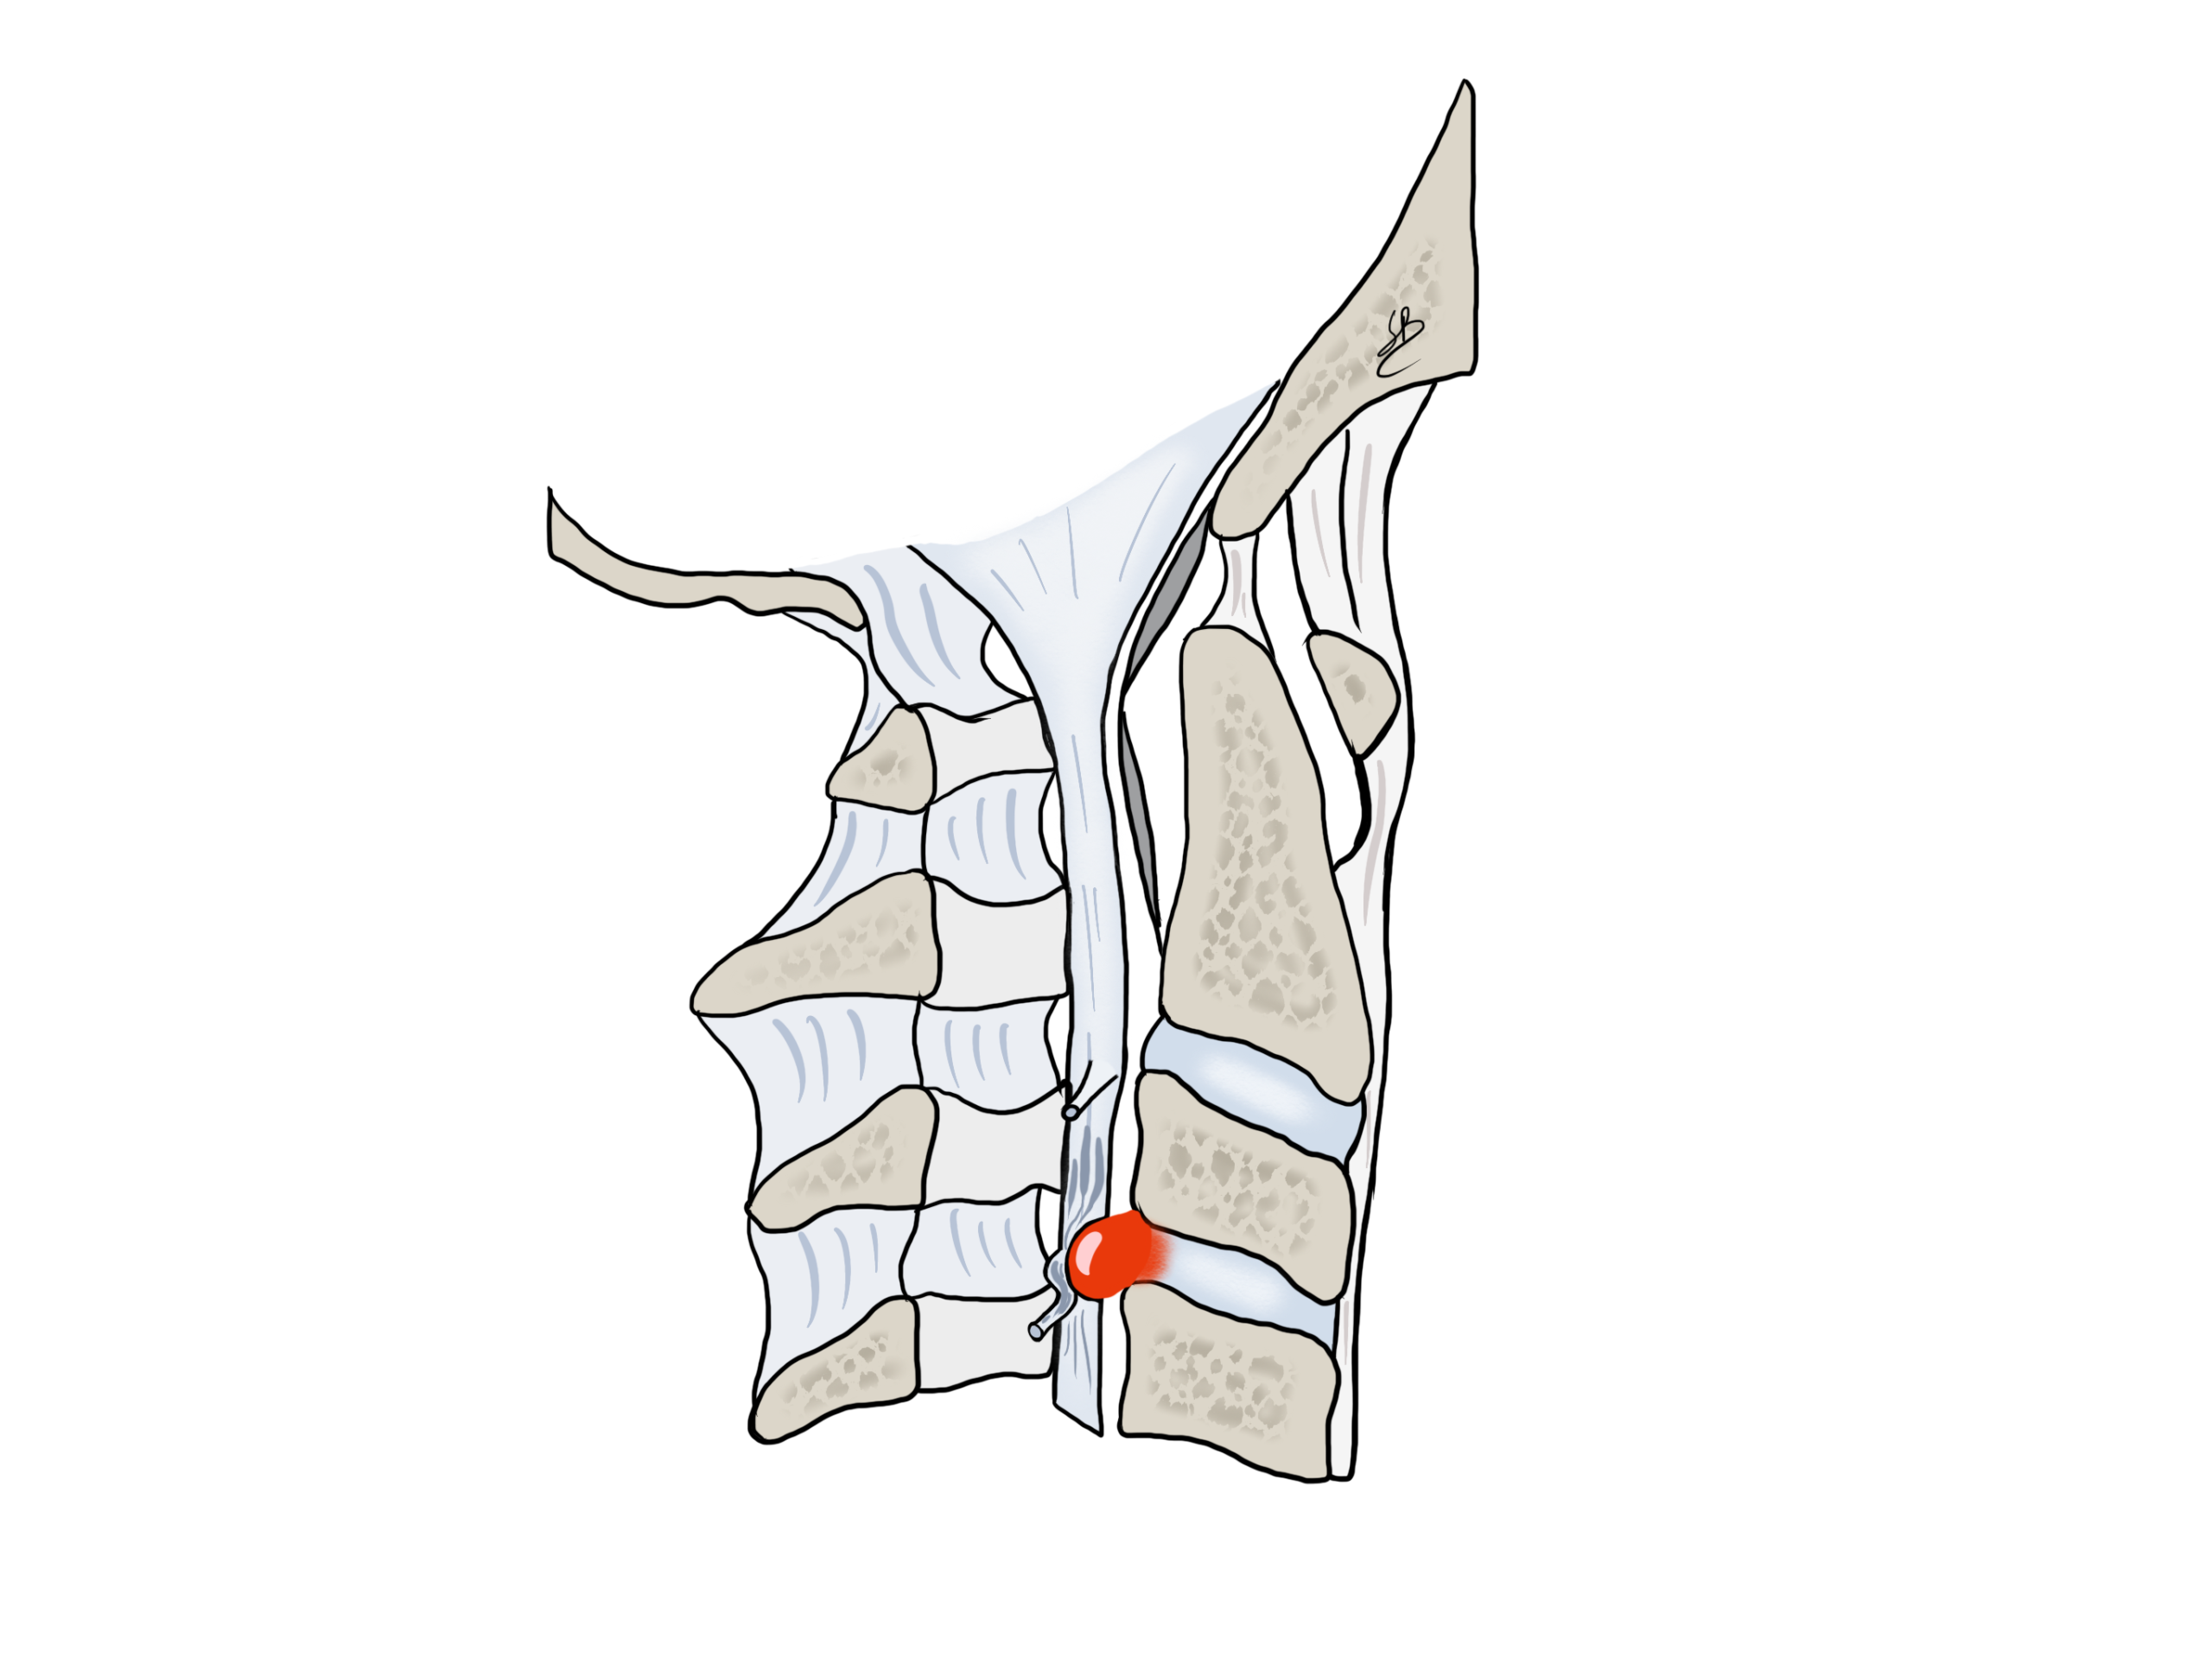

Un’ernia cervicale può schiacciare un nervo che va nel braccio, oppure comprimere il midollo spinale. Quando l’ernia viene a schiacciare un nervo, il paziente presenta un dolore nel braccio dovuto alla sofferenza oppure all’infiammazione del nervo. Nel caso di compressione midollare, possono presentarsi dei problemi neurologici più importanti, come la perdita della motricità delle gambe, delle braccia oppure un’incontinenza. Tutti questi sintomi fanno parte della sindrome di mielopatia cervicale.

Ernia discale con compressione radicolare

Nella maggior parte dei casi, un’ernia discale può essere trattata di maniera conservativa con dei farmaci antalgici, antinfiammatori oppure con un’infiltrazione attorno al nervo schiacciato. Tutti questi trattamenti hanno lo scopo di diminuire o eliminare l’infiammazione del nervo. Questo trattamento conservativo è controindicato in caso di deficit motorio oppure di sindrome di mielopatia.